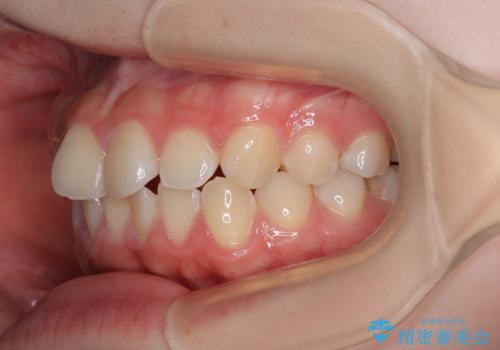

- 上下前歯部のデコボコを気にして来院された患者様です。

叢生は軽度であったため、マウスピースでもワイヤー装置でも対応可能でしたが、マウスピースを長時間使用する自信がないとのことでワイヤー装置にて矯正治療を行うこととしました。

叢生が軽度であったため、僅か半年で装置を除去することができました。